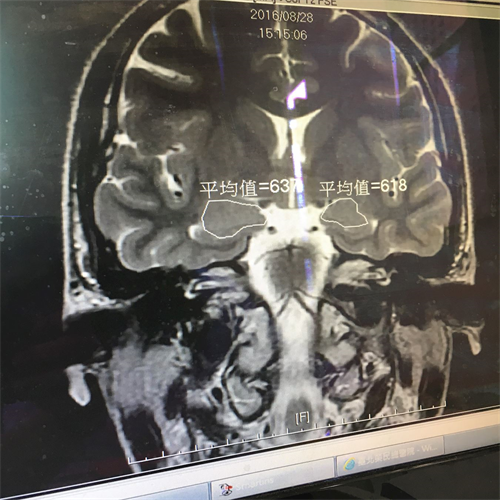

'图2:医院做核磁共振检查显示“脑部杏仁核肿大”。'

图2:医院做核磁共振检查显示“脑部杏仁核肿大”。

见她没有按时到医院回诊,医生打电话给母亲,千叮咛万吩咐要回诊做核磁共振,追踪检查,医生郑重叮咛:“不追踪不行喔。”玟君说:“我很清楚自己的身心状况,说不出有多感谢大法和李洪志师父出手搭救,我已经彻底摆脱可怕的惊恐,再也不需要吃药医疗了,不过;有机会我会回去医院向他们讲真相。”